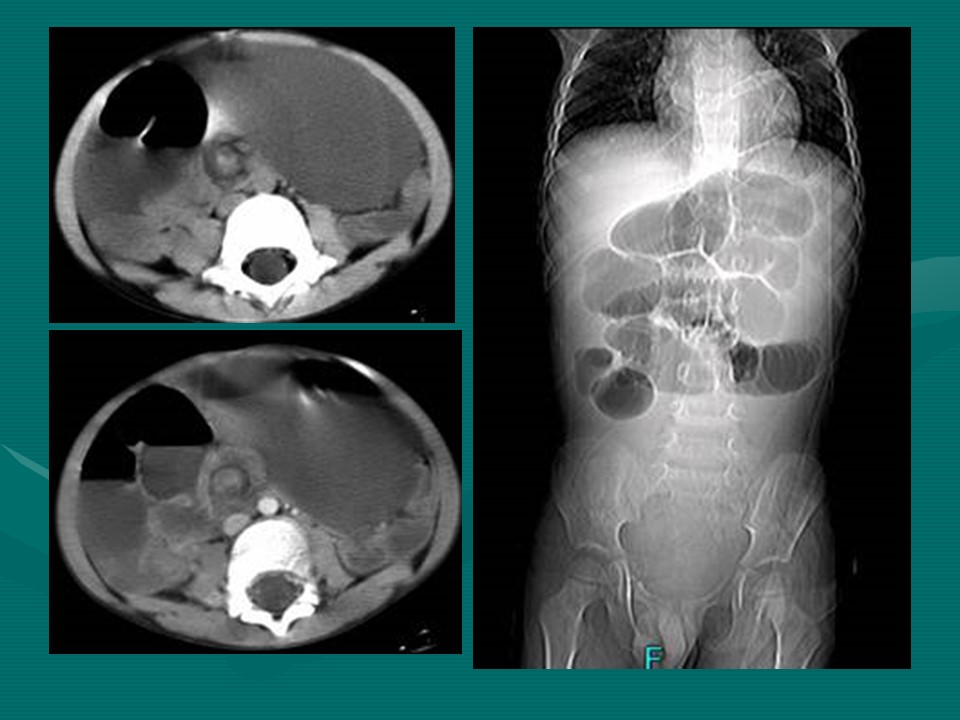

“肠梗阻的分类及影像诊断PPT” 的相关文章